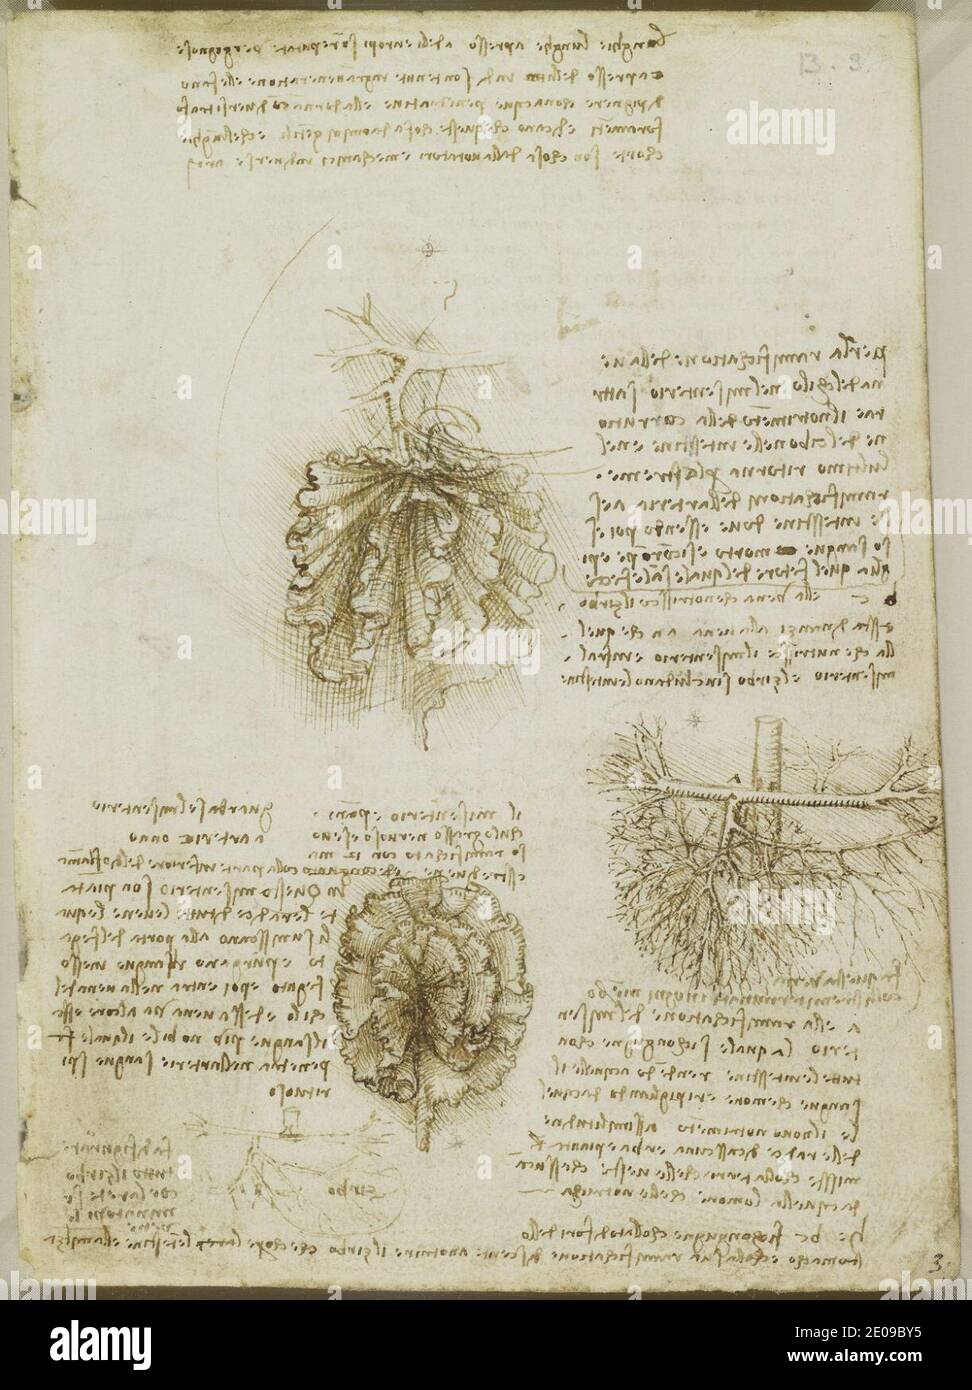

RM2E09C1Y–Leonardo da Vinci - Studien über die Blutversorgung der Gebärmutter und des Fötus, und Notizen über die Mechanik c.1510-13.